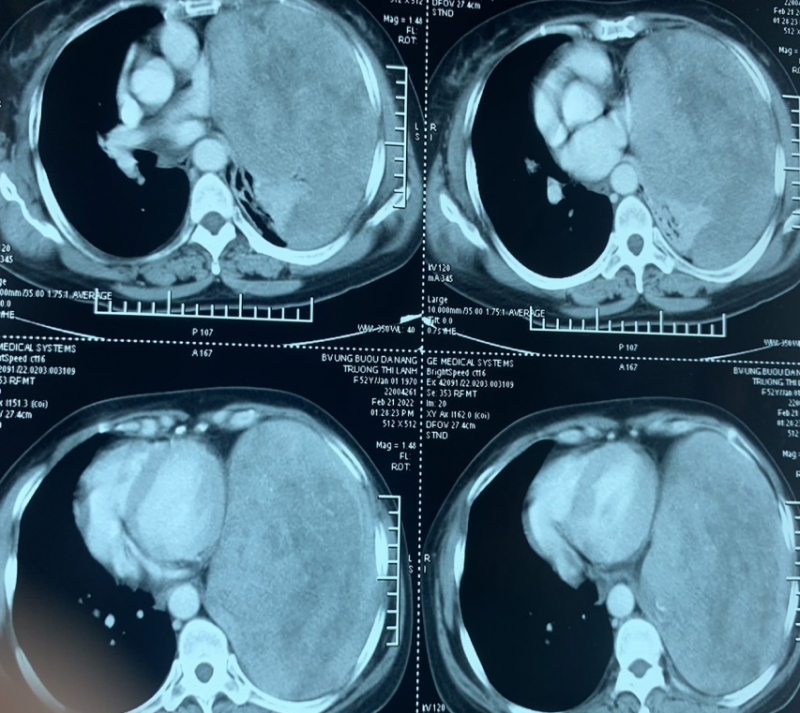

Được biết, bệnh nhân T.T.L được đưa vào cấp cứu trong tình trạng đau ngực trái và khó thở, qua các xét nghiệm kiểm tra: chụp CT ngực 128 lát cắt thấy khối u lớn ở trung thất kích thước lớn 25x35cm.

Các bác sĩ chẩn đoán bệnh nhân T.T.L bị u trung thất lớn chèn ép tim, phổi và có chỉ định phẫu thuật khẩn mở ngực trái qua khoang liên sườn VI trái để bóc tách khối u chiếm gần trọn khoang màng phổi trái, nặng hơn 3kg, bề mặt trơn láng, tăng sinh mạch máu, dính vào tim, phổi, cơ hoành.